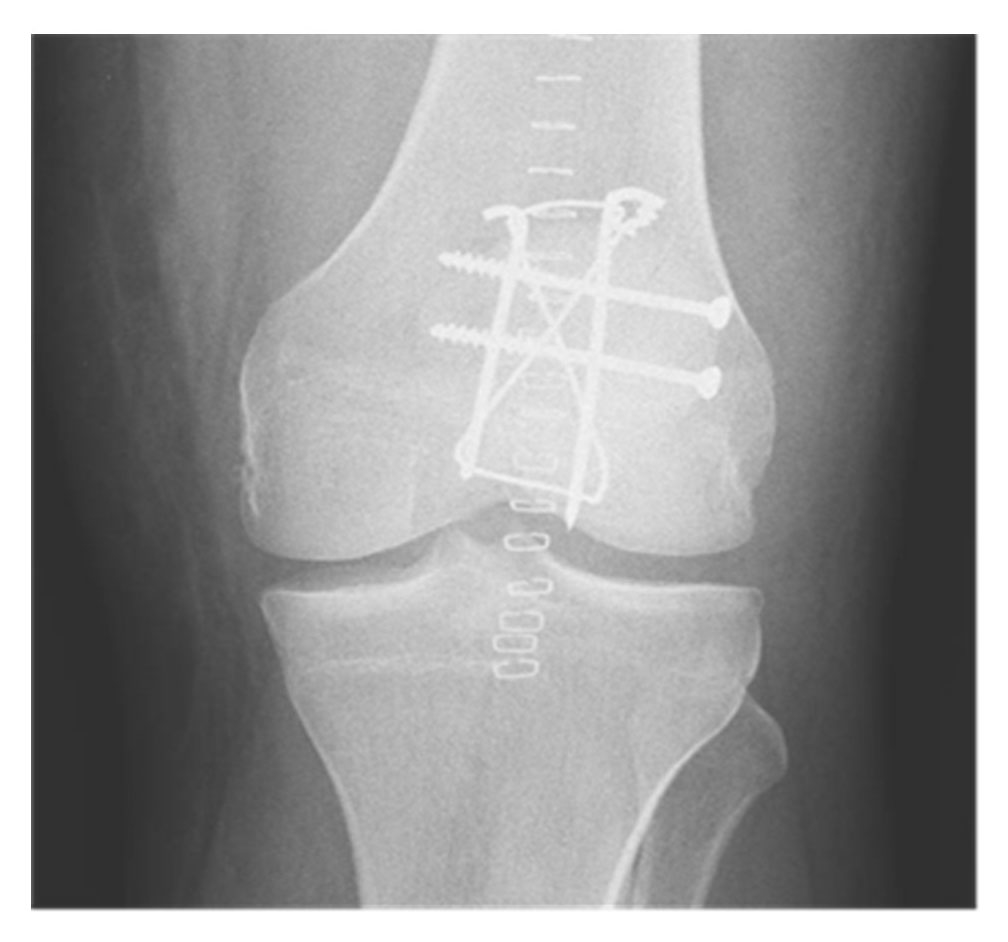

The most commonly used method is a tension band technique; however, this is only possible after a more complex fracture has been converted into a two‐part fracture and if there is no discontinuity on the articular side. Additional fracture fragments can be fixed using supplementary circular wire (fig. 4) [16] or mini‐fragment screws (fig. 5) [17]. The repair of the retinacular defect contributes also to the overall stability of the construct.

Figure 5 Tension band construct reinforced with an equatorial wire (CHUV).